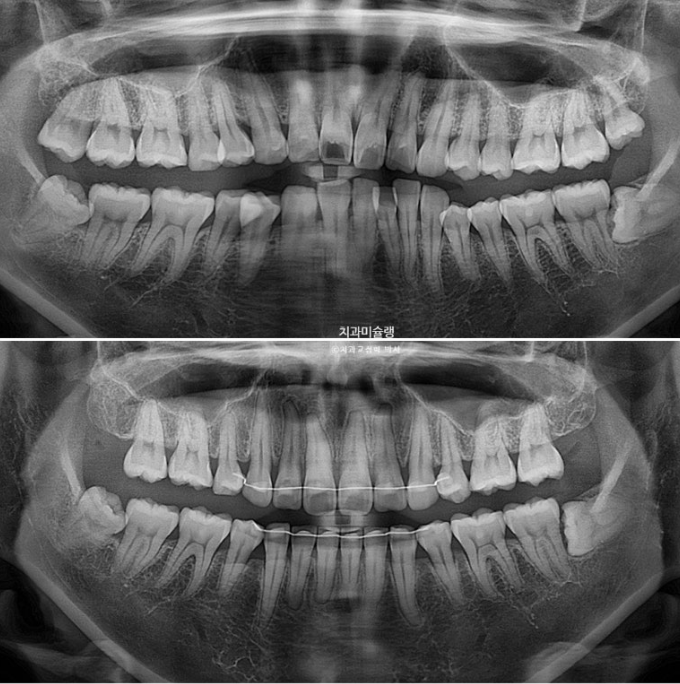

3년에 걸친 치료기간 동안 치근흡수는 없고 치근평행도는 양호합니다.

발치교정에서 전후 파놓라마 엑스레이를 반드시 첨부하는 이유는

인비절라인으로 뿌리이동은 안된다 라는 잘못된 정보를 듣고 오는 환자분들을 안심시켜 드리기 위함입니다.

아래 앞니는 계획대로 뒤로 1mm도 뒤로 들어감 없이 잘 유지가 되었고 위 앞니는 치조골이 허용하는 범위 내에서 아래앞니와 만나기 위해 최대한 뒤로 들어갔습니다.